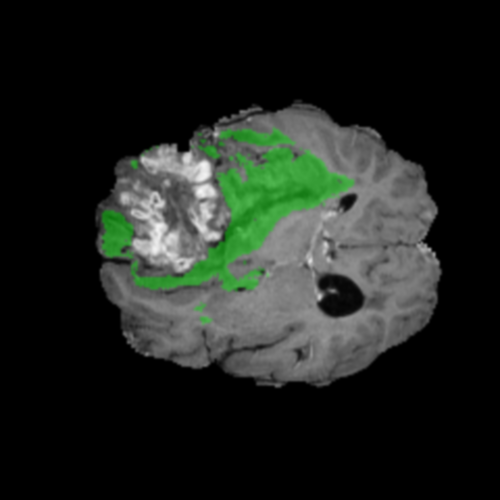

Ejemplos de Modalidades MRI

Visualización de las 4 modalidades de resonancia magnética y las segmentaciones de zonas tumorales utilizadas para entrenar el modelo

Núcleo HGG

Núcleo

Edema HGG

Edema

Realce HGG

Realce

Tumor Completo HGG

Tumor Completo

Núcleo Edema Realce

🎯 Zonas Tumorales Segmentadas

• Núcleo (NCR): Región central no viable y necrótica del tumor

• Edema (ED): Inflamación (acumulación de líquido) en tejido cerebral sano circundante

• Realce (ET): Parte activa y viable del tumor, identificada por captación del contraste en T1ce